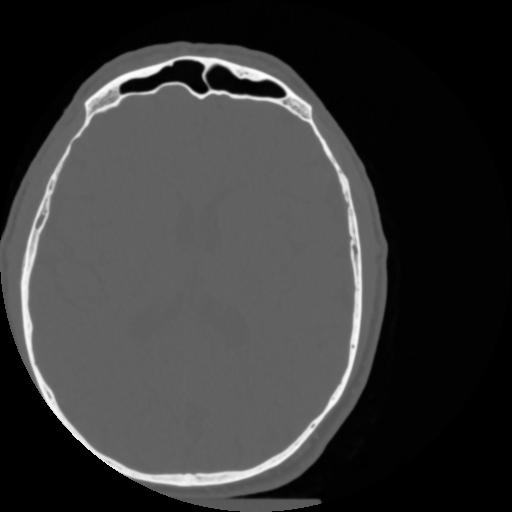

4 CEREBRO,,Vol,0.5,CEREBRO,,